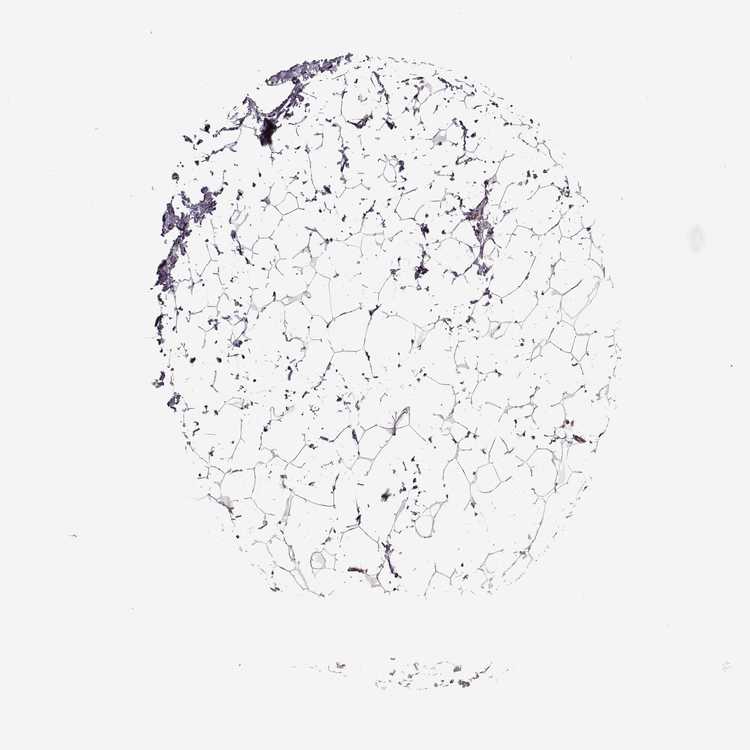

TISSUE PRIMARY DATA BREAST Show tissue menu

BREAST - Antibody stainingi

Antibody staining in the annotated cell types in the current human tissue is reported as not detected, low, medium, or high, based on conventional immunohistochemistry profiling in selected tissues. This score is based on the combination of the staining intensity and fraction of stained cells.

Each image is clickable and will lead to virtual microscopy that enables deeper exploration of all samples and also displays staining intensity scores, fraction scores and subcellular localization as well as patient and tissue information for each sample.

Antibody HPA068560

Adipocytes Not detected

Glandular cells High

Myoepithelial cells High